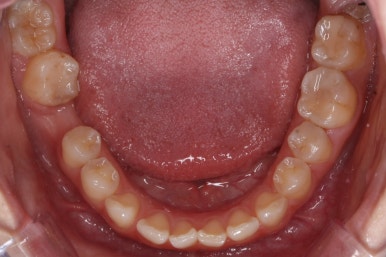

치료 과정을 순차적으로 보겠습니다.

임플란트를 식립하기 위한 공간이 서서히 확보가 되어 가는 것이 보입니다. 어금니만한 사이즈로 공간이 확보가 되면 식립이 이뤄지죠.

불과 4개월만에 장리가 충분히 확보된 모습입니다.

부산부분교정을 하기 전과 후의 모습입니다.

부분교정으로 하였기 때문에 다른 치아의 변화는 전혀 없습니다. 또한 비교적 짧은 기간으로 원하는 목표를 달성했죠.

부분교정으로 매우 만족스러운 결과를 이끌어 냈습니다.